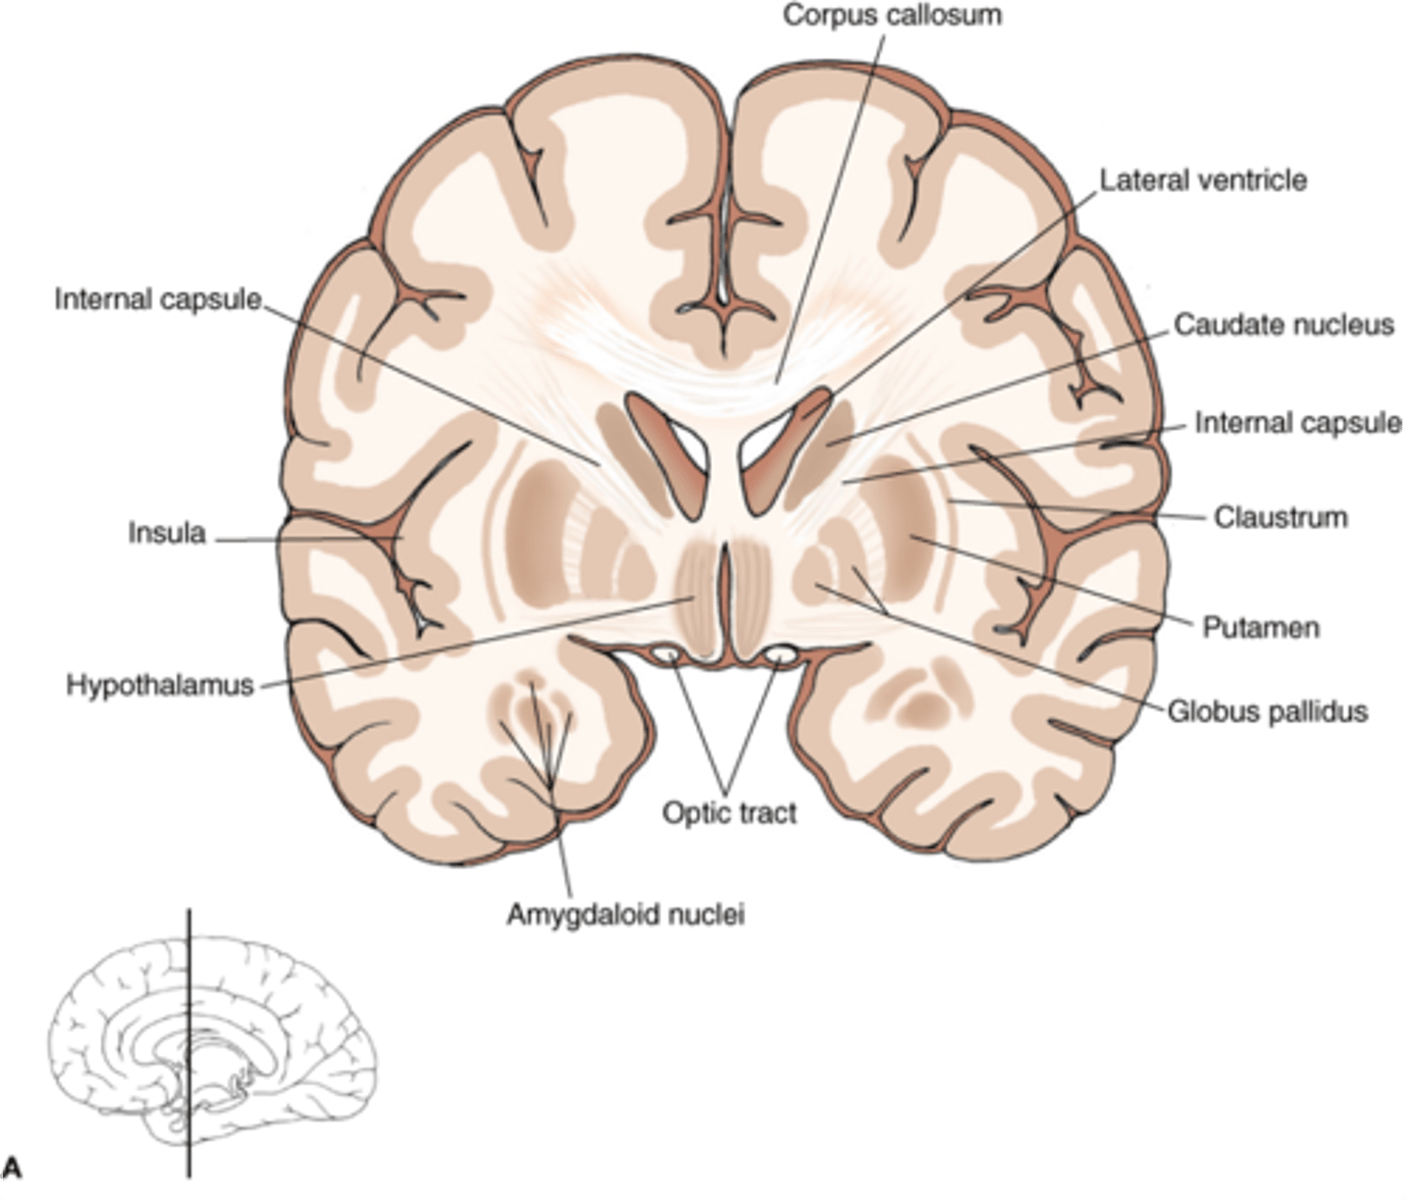

what are 3 key white matter structures found in the cerebrum?

1. corpus callosum

2. corona radiata

3. internal capsule

what cerebral white matter structure is a large bundle of nerve fibers that connects the left and right cerebral hemispheres, allowing them to communicate?

corpus callosum

what is the fan-shaped cerebral white matter sheet that is continuous ventrally with the internal capsule?

corona radiata

what cerebral white matter structure is a tract that carries sensory and motor information to and from the cerebral cortex?

internal capsule

what cerebral white matter structure is found between the basal ganglia?

internal capsule

what are the 3 regions of the internal capsule?

1. anterior limb

2. genu

3. posterior limb

what cerebral gray matter structure is a collection of subcortical nuclei primarily involved in motor control?

basal ganglia

what cerebral gray matter structure has a gate-keeping mechanism for the initiation of motor movement (choosing which actions to allow and which to inhibit)?

basal ganglia

what cerebral gray matter structure has roles in motor learning, executive functions, behaviors, and emotions?

basal ganglia

what are the 3 parts of the basal ganglia? what runs between them?

1. caudate nucleus

2. putamen

3. globus pallidus

internal capsule

what part of the basal ganglia is the C-shaped structure that is most medial?

caudate nucleus

what part of the basal ganglia is medial to the putamen?

globus pallidus

the putamen and globus pallidus of the basal ganglia are collectively called the _______________ nucleus

lentiform